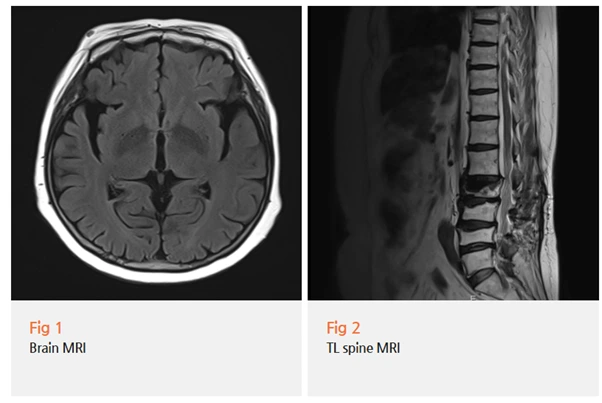

✔️ 신경학적 검사

✔️ Brain MRI 재검

✔️ 임상 증상 종합 평가

를 진행했죠.

결과는... 네, 파킨슨병이었어요.